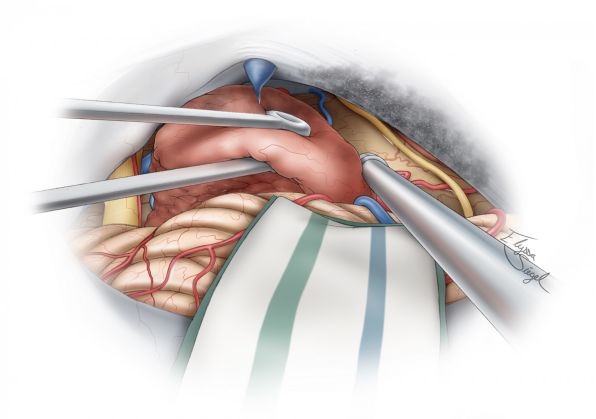

讨论技术原则之前,笔者先展示图1患者术中的一些截图。

图5. 左侧乙状窦后/侧方小脑上入路。注意富血供的岩骨表面硬脑膜(左上图)和小脑幕(右上图),岩上静脉已被切断;三叉神经自肿瘤下极分离(左下图);自小脑幕上肿瘤基底阻断其血供(右下图)。